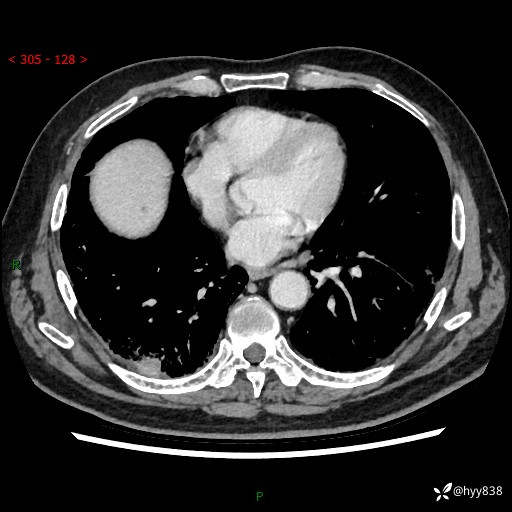

【检查】:胸部CT平扫+增强

【现病史】:患者半月前无明显诱因出现咳嗽、咳痰,为白色粘痰,无明显加重与缓解因素,伴气促,无发热,无大量脓痰,无胸痛、咯血,无哮鸣音,到我院就诊,胸部CT示右肺结节增大,并口服药物治疗无明显好转,具体用药不详,为求进一步治疗随来我院,经门诊以“孤立性肺结节”收入我科。 病程中患者精神、饮食可,睡眠不佳,大小便正常,体力下降,体重未见明显下降。

[既往史]:2022-06于当地第一人民医院确诊慢阻肺,现规律使用杰润(1次/日);2023-04-06于当地市第一人民医院行胸腔镜右肺上叶楔形切除术+右肺上叶切除术+淋巴结清扫术+胸膜黏连松解术,确诊为右肺鳞癌 pT2aN0M0 Ib期